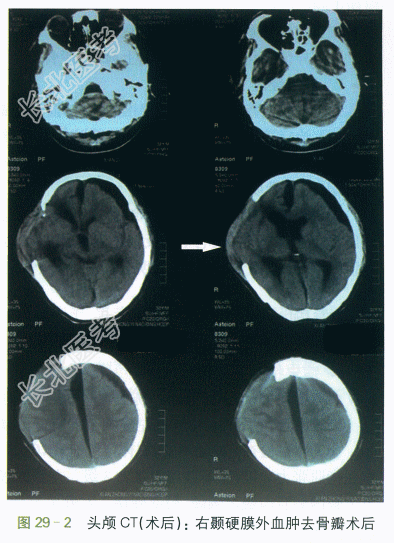

(2)影像学检查:①术前头颅CT示脑挫裂伤,右颞硬膜下血肿,左颞硬膜外血肿,左侧颞骨骨折,颅内积气,蛛网膜下腔出血,鼻窦炎,如图29-1所示。②术后头颅CT示右颞硬膜外血肿去骨瓣术后表现,脑挫裂伤,左筛窦及双蝶窦炎症,左侧颞骨骨折,如图29-2所示。③左膝关节片示左膝关节腘窝处异位骨化可能,如图29-3所示。④髋关节片示两侧髂前上棘及左侧股骨上段考虑异位骨化,左侧股骨头密度改变(考虑骨质疏松可能),如图29-4所示。